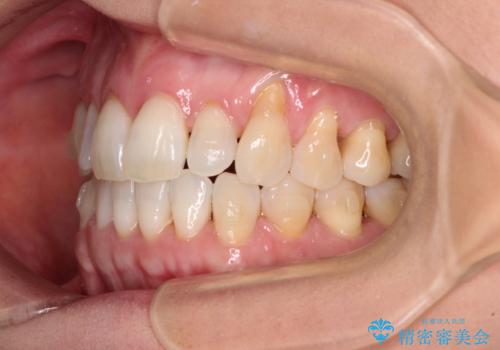

- 前歯の上下スペースによる食べにくさを気にして来院された患者様です。

インビザラインにより上下の前歯の隙間を閉じていくこととしました。

舌の突出癖があると上下前歯にスペースが開くため、矯正治療を機会に舌癖を改善するトレーニングを行ってもらい、矯正治療後の後戻りを防止するように指導しています。